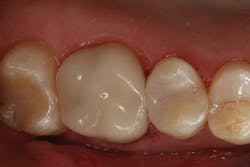

The clinical case in Figure 3 illustrates a patient who presented with a large, failing restoration containing cracks and decay. The patient was interested in an all-ceramic restoration. Occlusion was checked with articulating paper prior to treatment with a CAD/CAM restoration (figure 4). All previous restorative materials were removed from the tooth (figure 5). The tooth was restored using Grandio Core Dual Cure (Voco) build-up material (figure 6). A crown preparation was completed for a chairside CAD/CAM crown using the CEREC system (Dentsply-Sirona). The material of choice for this restoration was IPS e.max CAD (Ivoclar Vivadent), which is seen in Figure 7 after milling and in precrystallization form. The restoration was tried in and then polished, glazed, and placed in the oven for crystallization. The internal surface was then etched with 4.9% hydrofluoric acid, rinsed, and then coated with a silane coupler to create an optimal surface for bonding with the resin luting agent. The tooth was isolated and cleaned prior to etching. Once etched, the adhesive bonding agent (Futurabond U) was activated to mix the two liquids within the single-dose blister package. The blister seal was broken with the bonding agent brush and the adhesive was applied and agitated for 20 seconds. The adhesive was lightly dried for five seconds and then cured with an LED curing light for 10 seconds. A dual-cured adhesive resin luting agent (Bifix QM) was dispensed into the crown with its automix syringe (figure 8). The crown was seated and excess cement was removed after a two-second light cure. The tooth was then flossed and occlusion was checked (figure 9). The patient was very satisfied with the final result.

Figure 9: Completed restoration